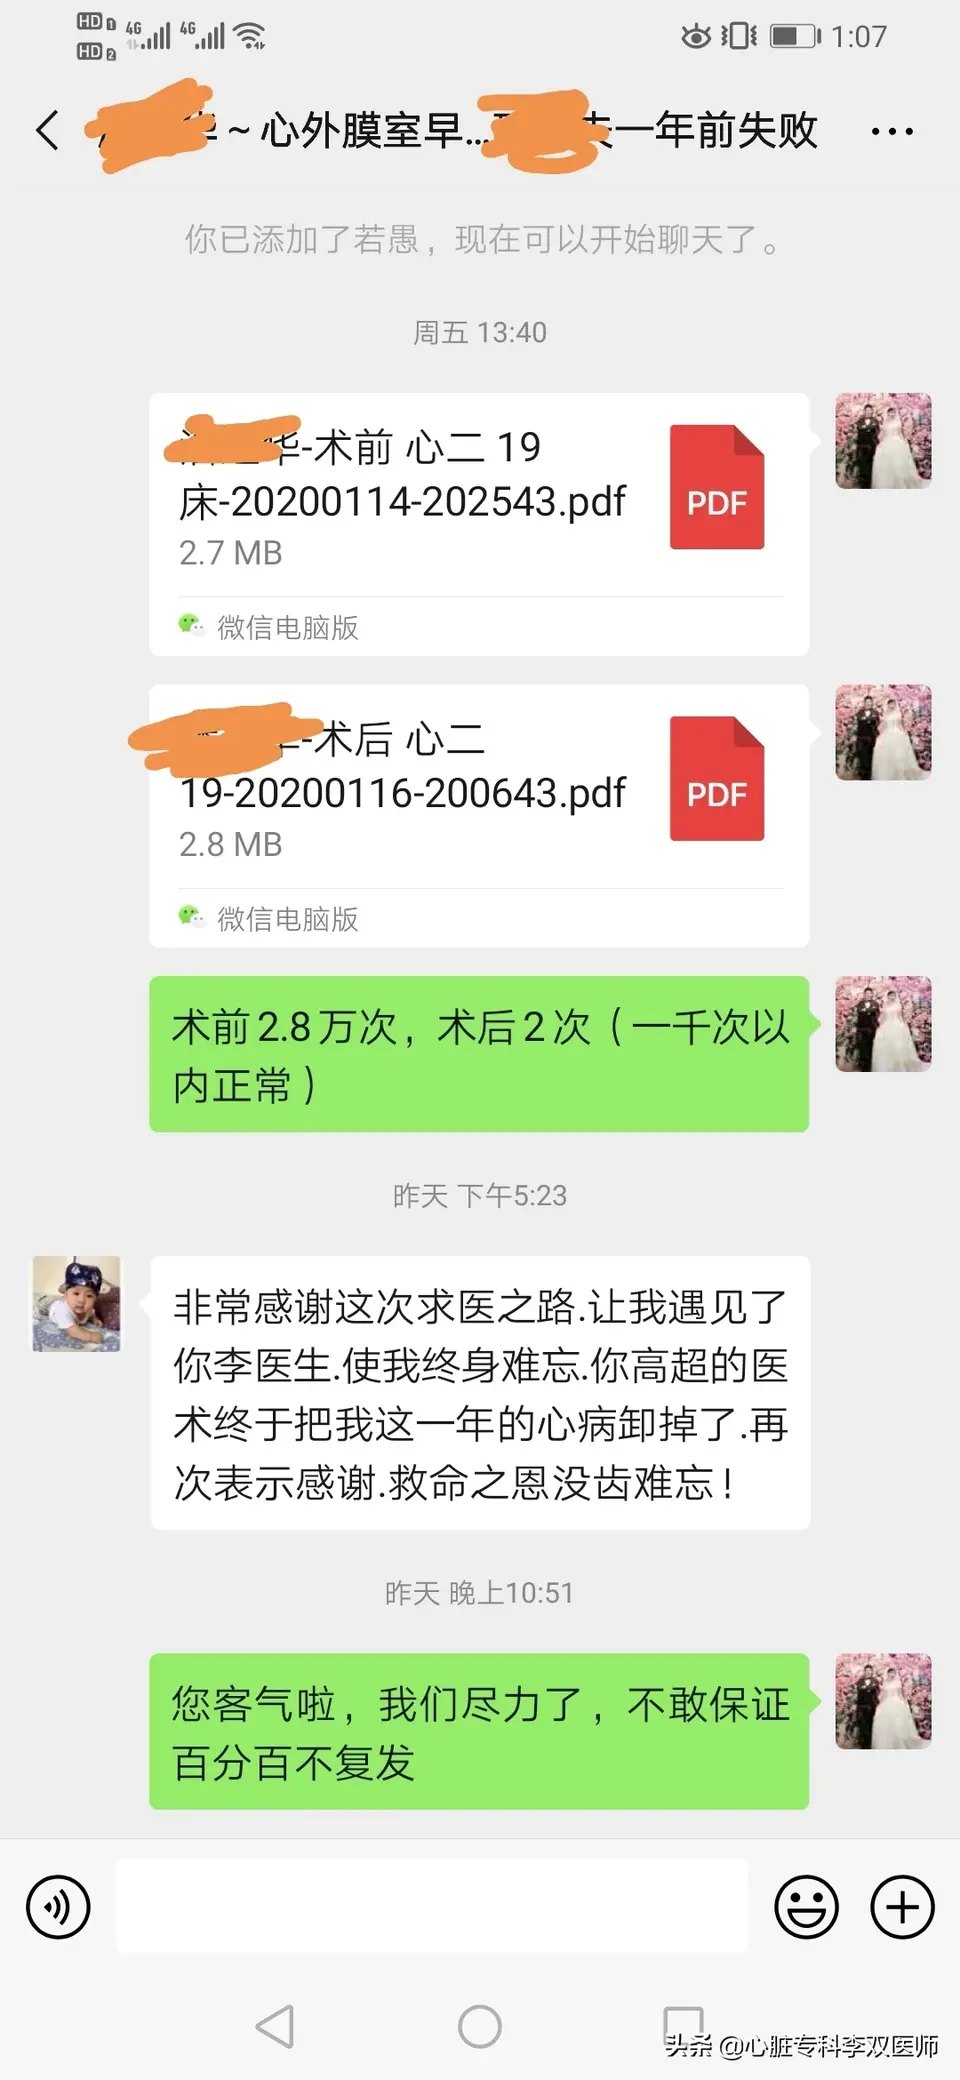

前天给一个外地来就诊的病人做了难度很高的“心外膜室早”消融的病例,病人一年前在杭州某三甲医院曾行消融失败,这一年来因为笼罩在“频发室早”的阴影下,患者有了明显的心理问题。这次我们标测的情况和上次外院消融情况完全一致,只是坚持又带有一点运气的在非传统的消融位置(解剖位置,而不是最早激动位置)尝试了消融,结果异常的顺利,术中忐忐忑忑观察了一小时无复发。今天患者顺利出院,术后24小时心电图提示的室早仅2次(一天的心跳是约10万次,1000次以内的早博没有意义),比机器的误差都小,而术前是1.4—2.8万次,是万!万!万!。坚持就是胜利,坚持带来好运!

昨天晚上患者发来了祝福,表示“把一年来的心病”解除了。